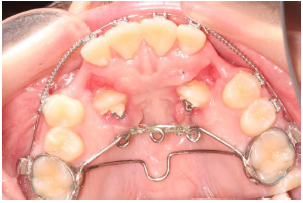

A palatal appliance “double transpalatal bar” was designed, which is comprised of a Transpalatal bar and a 3-helix bar. Both bars were soldered on first molar bands Figure 2. The purpose of the 3-helix bar is an anchorage for the elastic thread that pulls the impacted canines away from the roots of the incisors. After vertical eruption of canines, the 3-helix bar is cut, and the second transpalatal bar is left in place for anchoring the maxillary first molars (Figure 3A).

Figure 2: Modified transpalatal bar with the impacted canines being uprighted through the attachments from the lingual surface to the bar-helices.

Surgical exposure was carried out using a closed technique.

Eyelets (Ortho Technology) were bonded during surgery and

Elastic Threads (Ortho Technology), pulling the impacted canines

from the roots of the incisors started, were fixed on the helices. Flap

was closed and changing the elastic thread was carried out every

three weeks (Figures 3A-E).